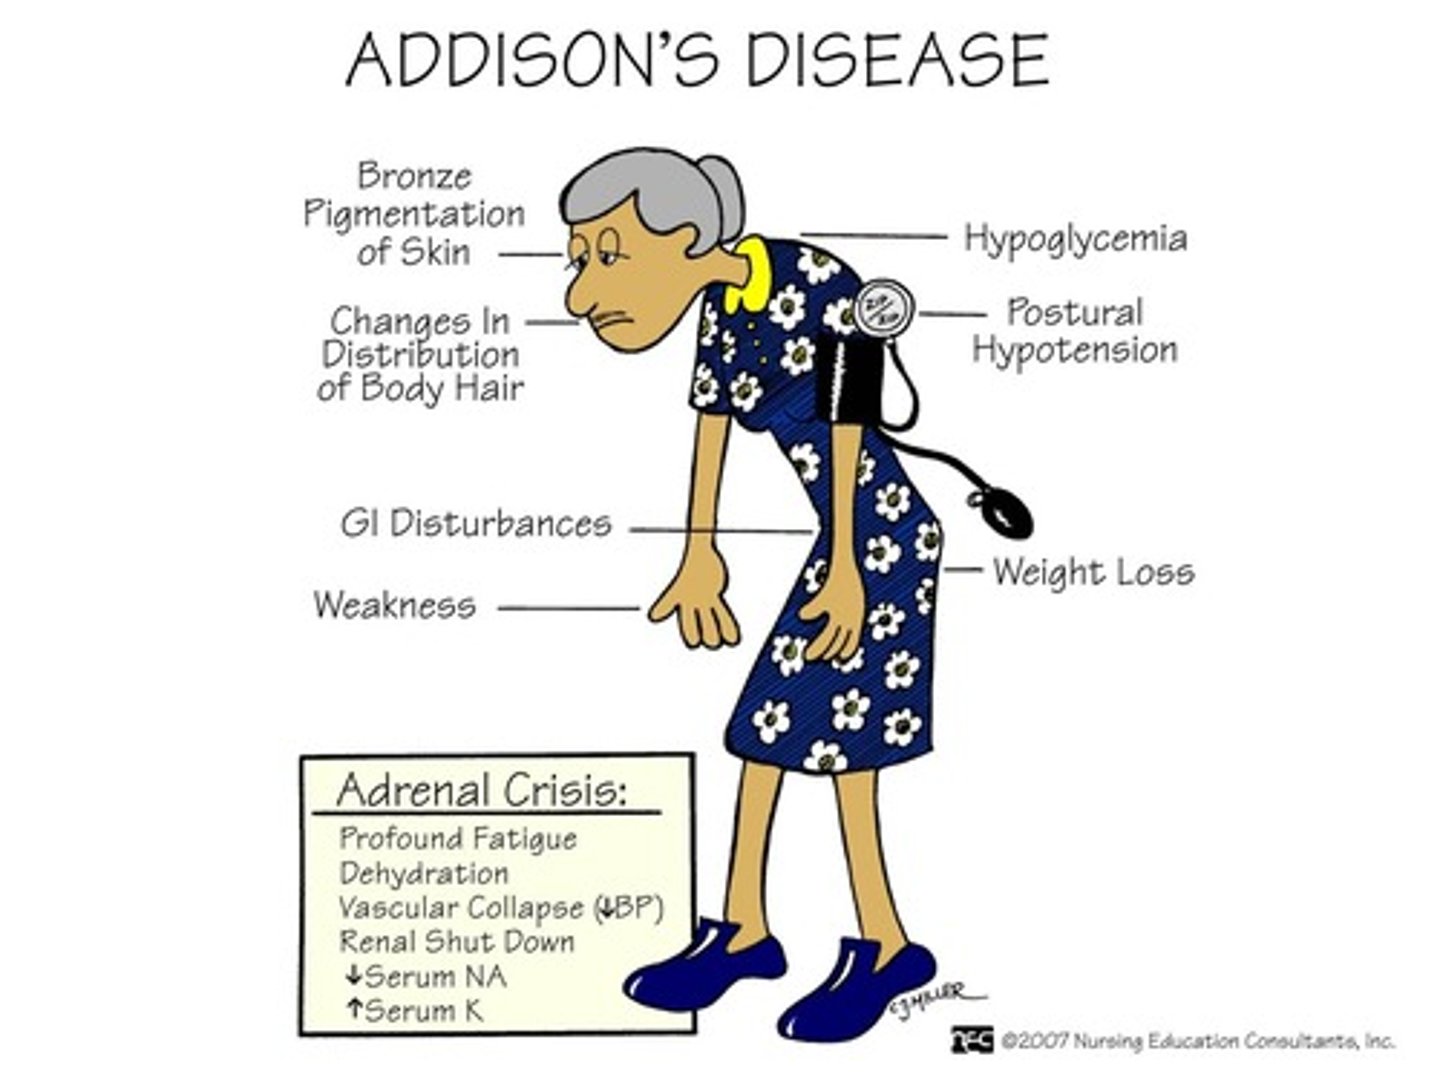

Acute adrenal insufficnecy is also known as ____disease. A patient on steroids might have an attack if not supplmeneted by ___ the steroid dose before dental treatment due to thier inability to produce extra ___ in response to stress

addisons disease

doubling the dose of steroids

cortisol in response to stress